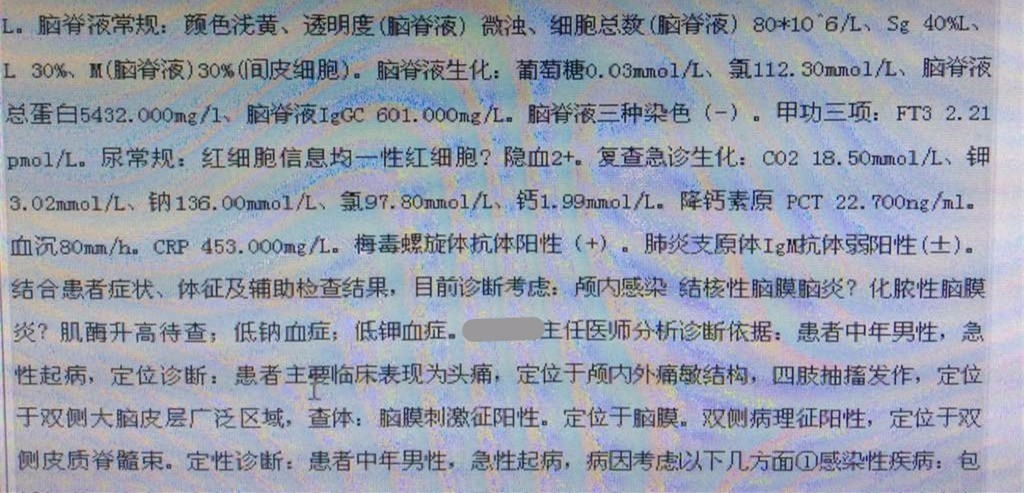

2016-3-24血常规示,白细胞计数10.35×109/L,淋巴细胞百分比1.4%,中性粒细胞百分比93.2%,中性粒细胞绝对值9.65×109/L。

2016-3-25生化全项示,AST47.5U/L,GGT128U/L。血沉80mm/h,CRP453mg/L。

2016-3-26甲功三项(-),术前四项(-),梅毒螺旋体抗体(+)。

2016-3-25腰穿压力>300mmH2O,细胞计数80×106/L,脑脊液蛋白5.432g/L,葡萄糖0.03mmol/L,氯化物112.3mmol/L,脑脊液IgG601mg/L。脑脊液墨汁染色(-),抗酸染色(-),间皮细胞30%,单核细胞30%,多核细胞40%。